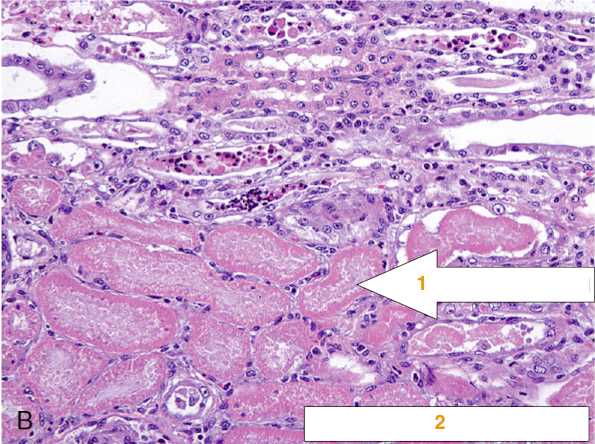

Name the following features in the diagram below, organ location and the type of necrosis:

The architecture still exists however however cells have no nuclei

See histological image below: